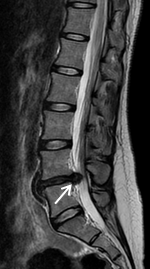

術前MRIでは腰椎椎間板ヘルニアを認め、神経の圧迫を認めています。後方からのヘルニア摘出術により神経症状は劇的に改善しました。

術前MRIでは脊柱管の狭窄を認め、神経の圧迫を認めています。後方からの除圧術後、神経への圧迫は改善しています。